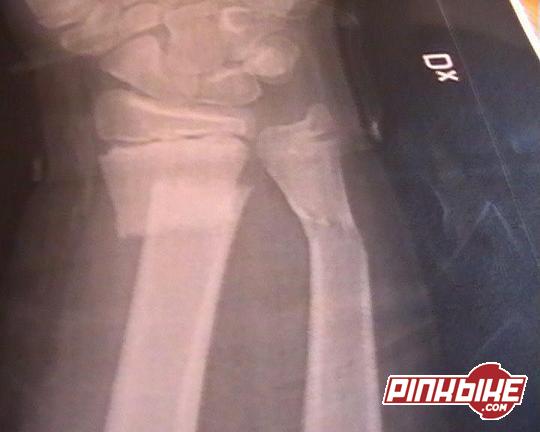

läkarna fick sätta ihop ankeln med 3 skruvar då jag bröt av de på mitten hehe